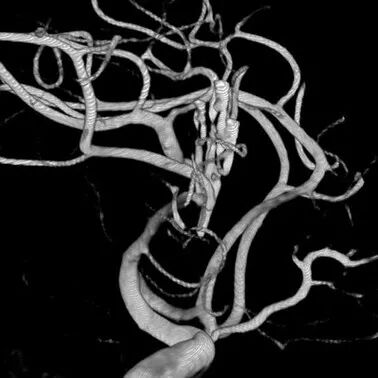

图3. 患者手术后复查全脑DSA情况。3D-DSA提示动脉瘤完全夹闭,瘤夹位置理想,M1载瘤血管及分叉部颞前动脉和M2主干血流通畅。

图6. 患者手术后复查全脑DSA情况。3D-DSA提示动脉瘤完全夹闭,瘤夹位置理想,M1载瘤血管及分叉部颞前动脉和M2主干血流通畅。